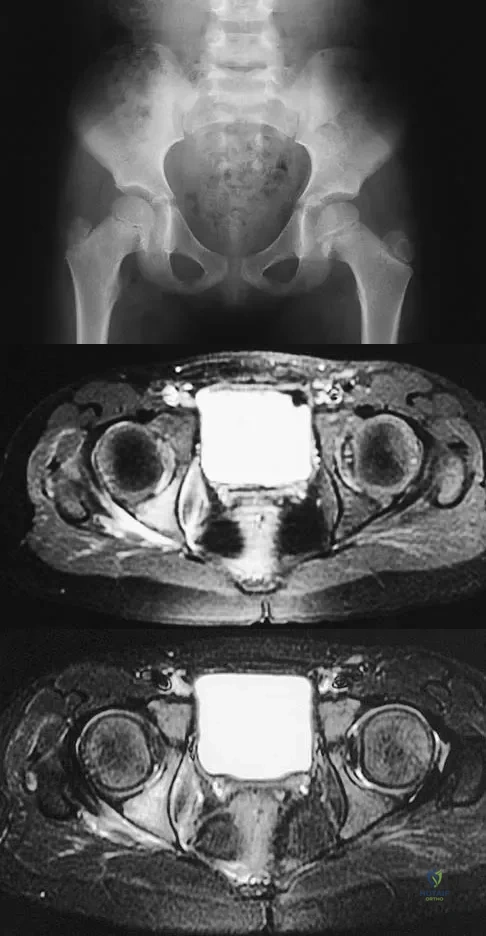

Question 80

A 5-year-old girl has had a low-grade fever, right hip and buttock pain, and a right-sided limp for the past 5 days. Examination shows diffuse tenderness and extreme pain on range of motion of the hip. Laboratory studies show a peripheral WBC count of 13,500/mm3 and an erythrocyte sedimentation rate of 55 mm/h. A radiograph is shown in Figure 46a, and an axial postgadolinium T1-weighted MRI scan with fat suppression and an axial T2-weighted fast spin echo MRI scan are shown in Figures 46b and 46c. What is the most likely diagnosis?

Explanation